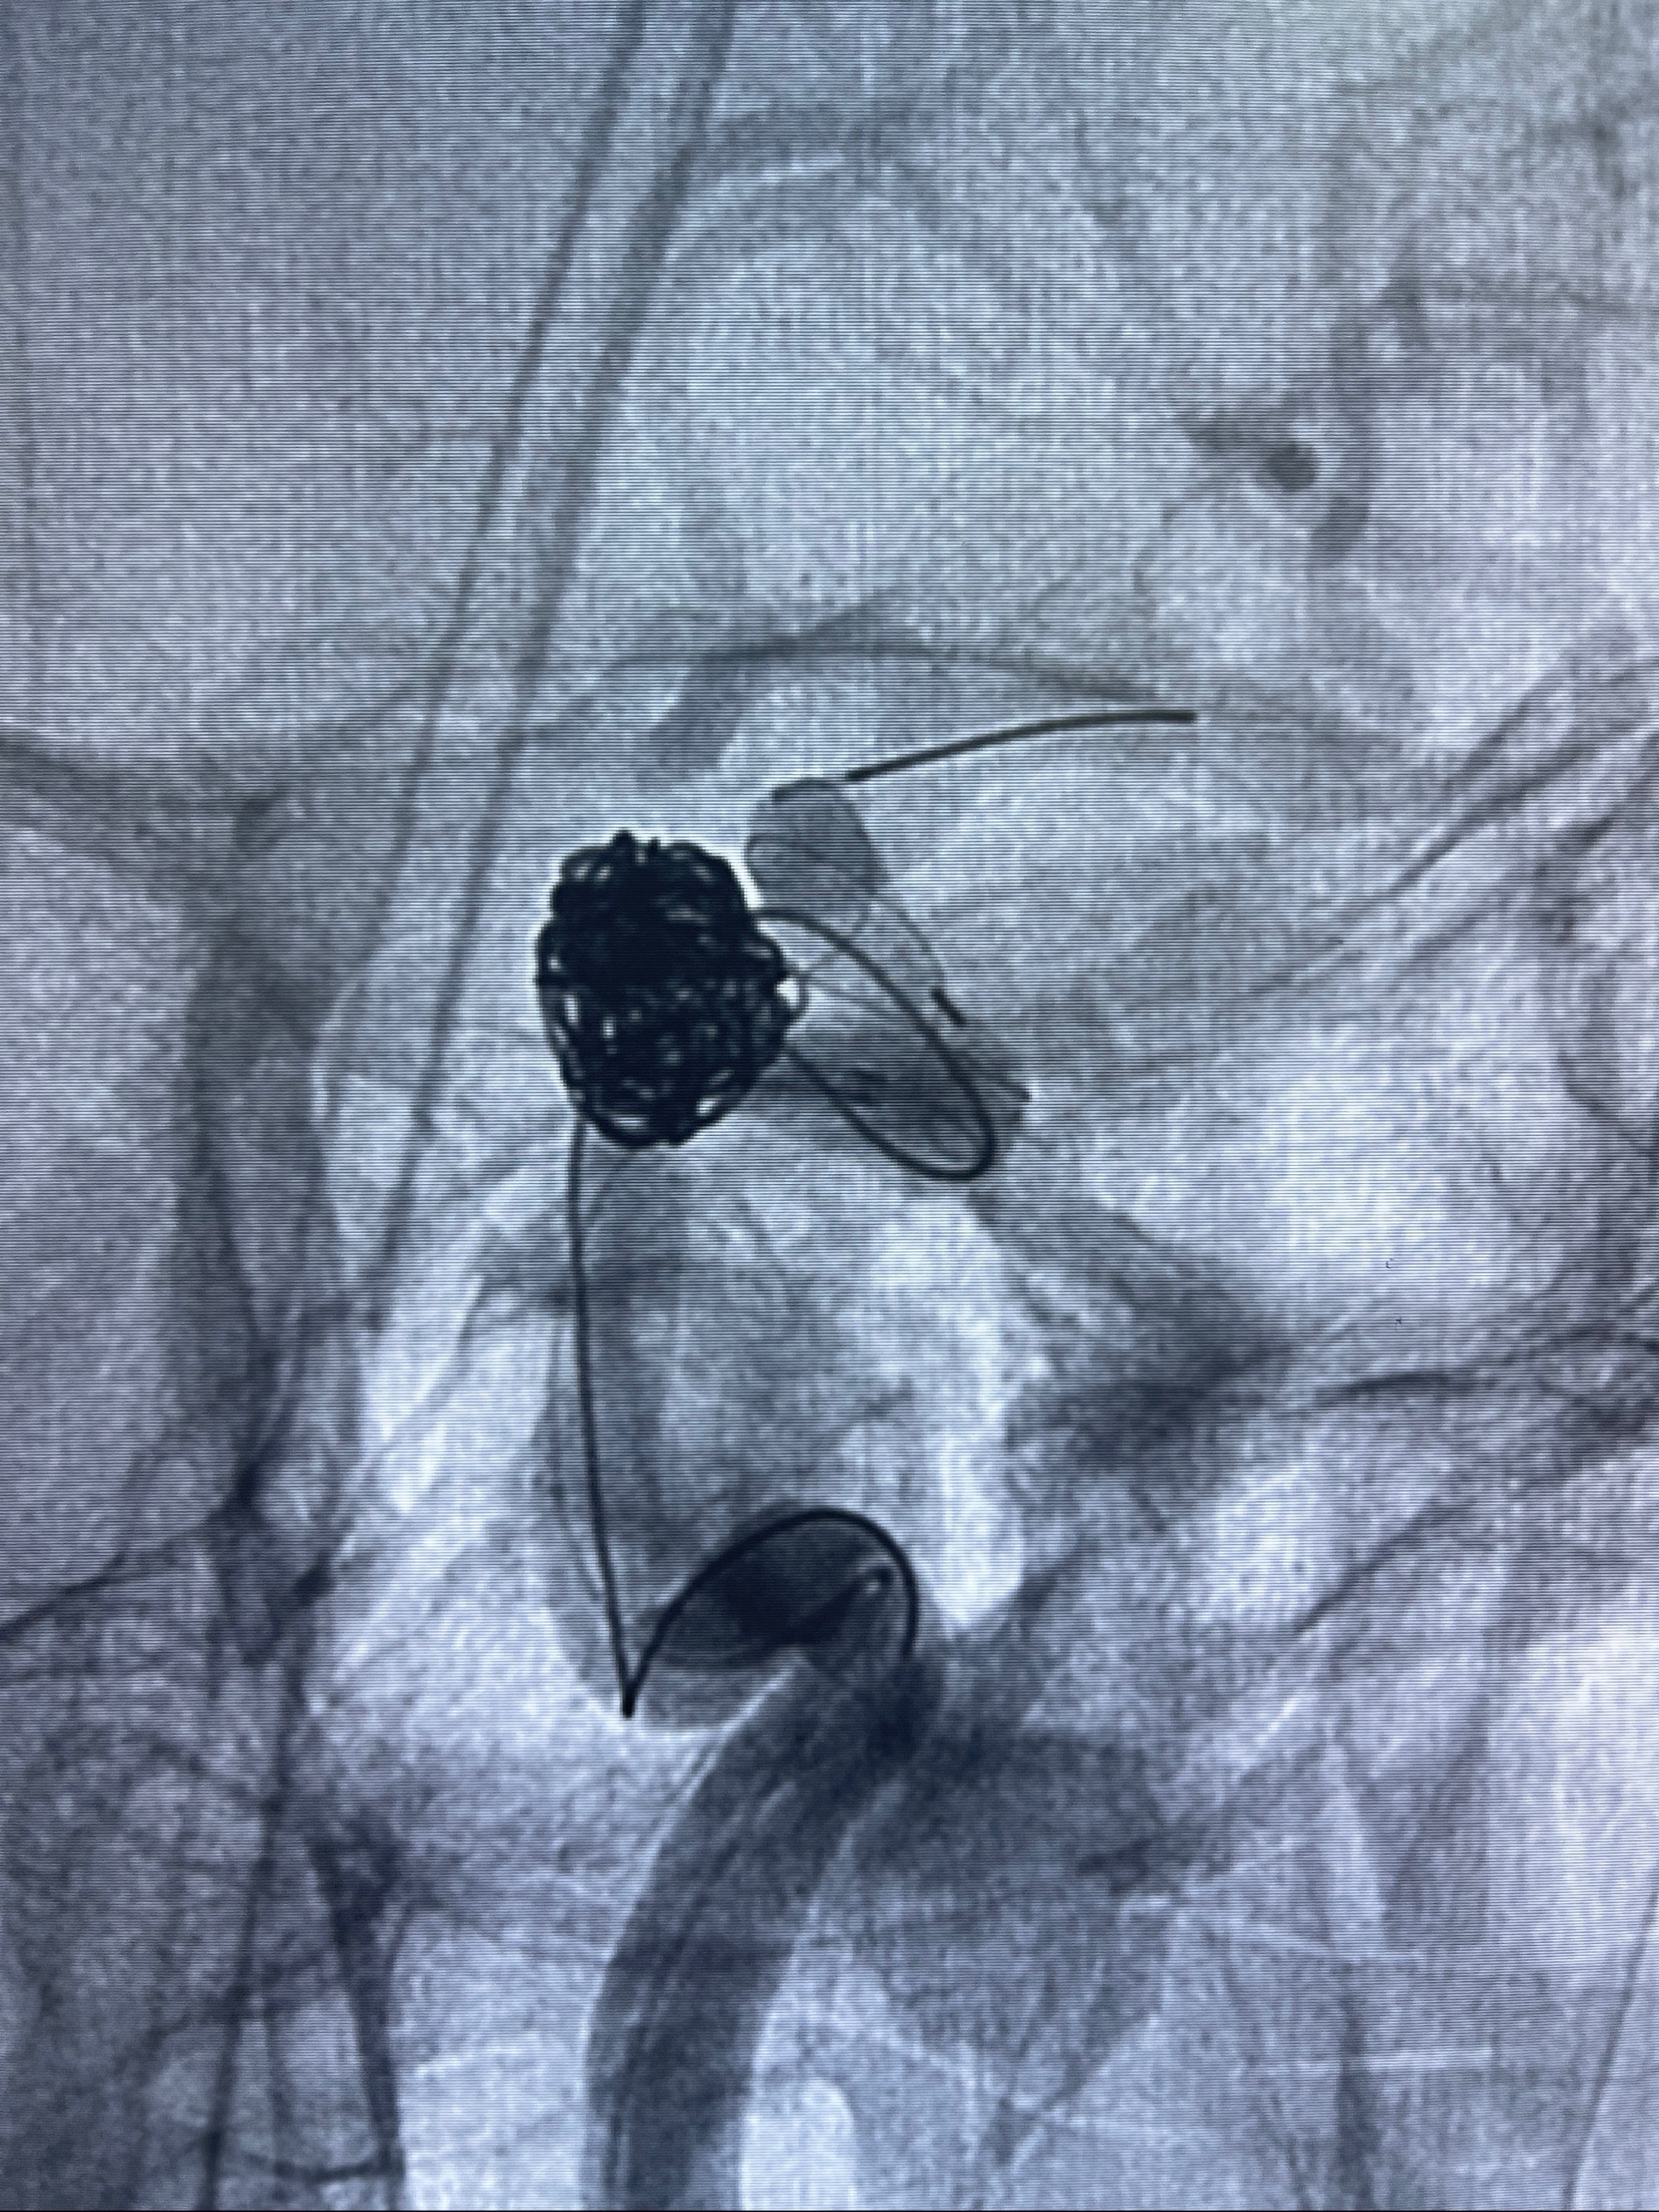

- Tubridge 4.0-20mm密网支架

- 加奇微弹簧圈:7*30/6*20/5*20/2*8

术后3D显示支架贴壁佳